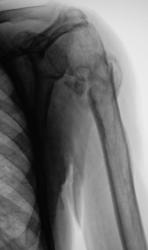

Пациент направлен в рентгеновский кабинет для рентгенографии плечевого сустава. Травма. Произведена рентгенография в прямой проекции.

2.Perelom.1..JPG

После наложения гипсовой повязки, хирургами пациент на контроль направлен не был.

После снятия гипсовой повязки, пациент направлен на "рентген-контроль" для анализа процесса консолидации.

картина посттравматического остеомиелита.

Я не уверен, что есть признаки остеомиелита, скорее можно предположить резорбцию костной ткани в месте перелома в счетании с формированием костной мозоли.Важна клиника (при остеомиелите следут ожидать гипертермию). Сколько прошло времени между сериями снимков?

1,5 месяца.

Учитывая наличие хорошо выраженной мозоли может и зарастет, но не очень нравится местоположение отломка медиально, вероятно с ним будут "проблемы".

О консолидации говорить нельзя.